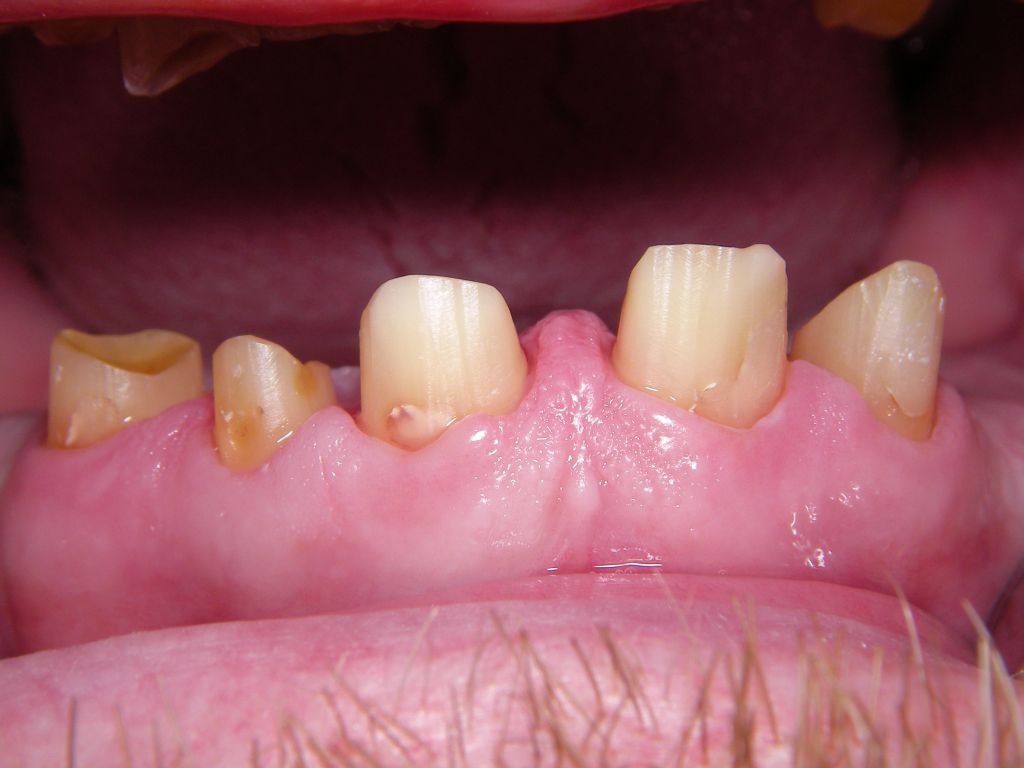

Hier ein einfacher Fall, bei dem keine besondere Vorbehandlung notwendig war. Der Patient, 58jährig, suchte die Praxis erstmals im September 2005 auf. Es erfolgten mehrere prothetische Planungen, der Gutachter des "Medizinischen Dienstes der Krankenkassen" (MDK) wurde noch von der Krankenkasse in Anspruch genommen, was heute bei größeren Planungen der Regelfall geworden ist. Umgesetzt wurde dann eine für einen solch großen Fall preisgünstige Lösung von 6434 Euro Gesamtkosten (4264 Laborkosten, 2170 Honorar). Die Krankenkasse übernahm als Festzuschuß 3843 , für den Patienten verblieben 2591. Im Januar 2006 ging es dann endlich los - zunächst allerdings beim Kieferchirurgen, weil wegen einer erhöhten, medikamentös bedingten Blutungsneigung es sicherer erschien, einige Zahnentfernungen von diesem durchführen zu lassen. Ausgangsbilder: |

Die Bilder können alle angeklickt werden! Das Hauptproblem dieses Falles lag im Oberkiefer - die über die Jahrzehnte abgeknirschten, kurzen Zähne erschweren Kronen, die durch eine Prothese belastet werden können. Die gewählte Lösung besteht darin, die Zähne nur rundherum zu beschleifen, aber nicht mehr zu kürzen und die Prothese mit einem Druckknopfsystem an die Zähne anzukoppeln, das ein "Spiel" aufweist, so daß die Prothese nicht als Hebelarm auf die schwachen Restzähne wirken kann. Rechts die beschliffenen Zähne kurz vorm Zementieren der Kronen. |